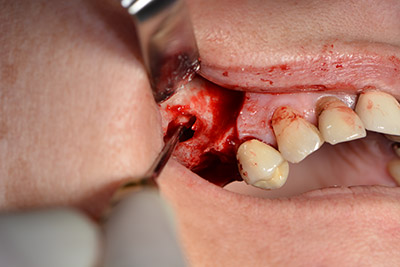

Im nächsten Schritt wird die Sinusbodenelevation mit simultaner Implantation durchgeführt. Für die bukkale Fensterung der Kieferhöhlenwand gibt es auch hier bei der Implantmed an der ersten Position eine Voreinstellung.

Mit 35.000/min wird das Fenster angelegt und anschließend die Schneidersche Membran nach kranial präpariert. (Abb. 13 bis 14).

Danach wird das Implantat eingebracht und der Knochen aufgebaut. Aufgrund der Größe des Augmentates wurde im vorliegenden Fall Eigenknochen, der als Bohrspäne bei der Implantation 16 und der Fenestration 14 angefallen ist und mit einer Knochenfalle aufgefangen wurde, mit Knochenersatzmaterial vermischt.